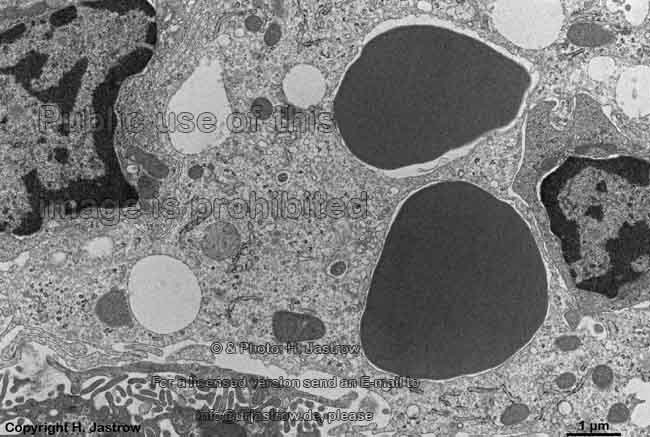

Miniaturbildübersicht Leber (Hepar):

Bereits bezeichnete Abbildungen lassen sich durch Anklicken des Textes aufrufen!

Hepatocyten, ITO-

Zelle, Sinusoid (Affe)

Hepatocyten, Kupffer-

und ITO Zelle (Affe)

A. Hepatozyten (Terminologia histologica: Hepatocyti; englisch hepatocytes) sind die funktionstragenden Zellen der Leber und werden auch Leberparenchymzellen oder Leberepithelzellen genannt. Diese mit Durchmessern von 20 - 30 µm relativ großen polyedrischen Zellen mit mehr als 6 Seiten bilden plattenförmige Zellverbände (Terminologia histologica: Laminae hepatocyticae; englisch: hepatocyte laminas, hepatocytic plates, hepatic trabeculae), die in einem zusammenhängenden dreidimensionalen Zellnetzwerk (Terminologia histologica: Muralium hepaticum; englisch: hepatic muralium) in etwa parallel zueinander stehend verbunden sind. Dazwischen verzweigen sich die Sinusoide. Ca. 20 - 25% der sehr stoffwechselaktiven Zellen weisen 2 Kerne auf. Zwischen 3 - 40 % der Zellkerne haben Durchmessern von 10-12 µm und sind diploid (normaler, doppelter Chromosomensatz); sie finden sich am häufigsten im periportalen Bereich der Zone 1; 50 - 60% haben Kerndurchmesser von ~ 15 µm und sind tetraploid (4-facher Chromosomensatz) und die besonders großen Kerne mit Durchmessern von ~20 µm sind sogar oktaploid (8-facher Chromosomensatz). Hepatozyten enthalten in etwa 500 200 - 800 nm durchmessende Peroxisomen, die an der Cholsterin- und Gallensäuresynthese beteiligt sind

B. Sinusoidendothelzellen(Terminologia histologica: Endotheliocyti perforati; englisch: perforated endothelial cells): Die platten Endothelzellen der Lebersinusoide bilden ein diskontinuierliches Endothel mit vielen, teils deutlich über 100 nm weiten, Lücken aus, unter dem sich keine Basallamina findet. Benachbarte Endothelzellen überlappen sich, sind aber nicht über Zonulae occludentes miteinander verbunden. Die Zellen enthalten zudem einige hundert offene transzelluläre Poren mit ca. 100 nm Durchmesser, die oft eng nebeneinander liegen und Siebplatten ausbilden.

C. von Kupffer-Zellen (Terminologia histologica: Macrophagocyti stellati; englisch: stellate macrophages): Diese zum monozytären Phagozytensystem gehörenden Zellen sind große Freßzellen (Makrophagen), die sich im Lumen der Sinusoide im strömenden Blut befinden und mit einigen Füßchen (Pseudopodien), die sie durch Löcher in und zwischen Endothelzellen hindurchstrecken, im Disse-Raum verankert sind.

D. ITO-Zellen (Terminologia histologica: Cellulae perisinusoidales; Cellulae accumulantes adipem; englisch: Ito-cells, perisinusoidal cells, fat storing cells, hepatic stellate cells). Diese dreidimensional sternförmigen an ihren vielen großen zytoplasmatischen Lipidtropfen erkennbaren Zellen dienen der Speicherung von Vitamin A und Fett.